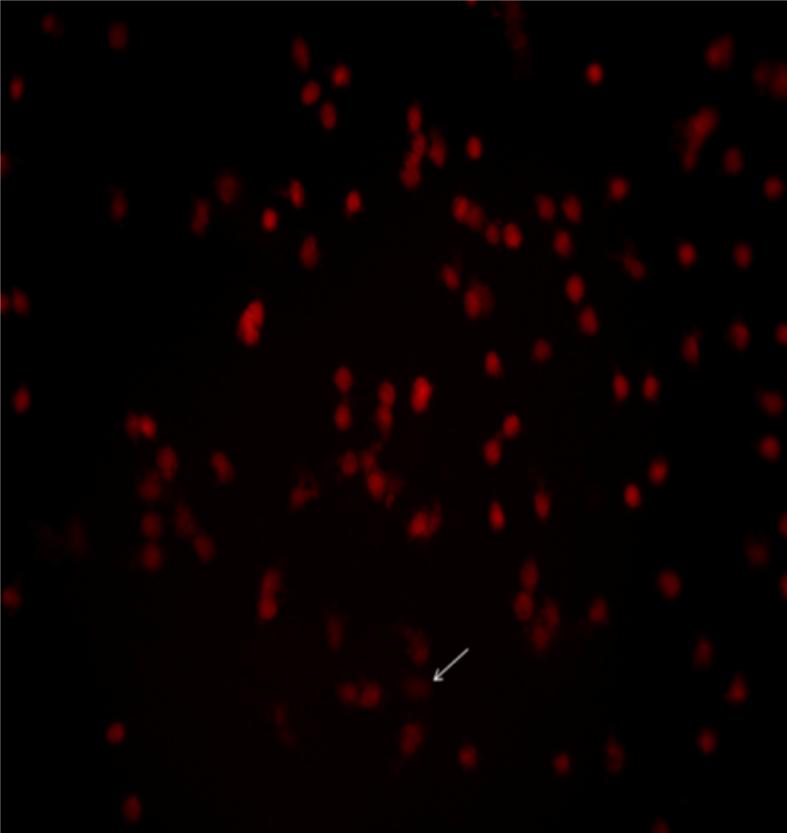

Metabolic syndrome (MS) is a cluster of metabolic abnormalities. Obesity and MS are always accompanied by elevated oxidative stress which might affect cellular bio-molecules such as DNA. The aim of the present study is to investigate DNA damage profile in obese premenopausal women and its relation to the risk of MS, polycystic ovary syndrome (PCOS) and history of recurrent pre-eclampsia. The study included 90 obese women included cases with MS (n = 30), PCOS (n = 30) and previous history of recurrent preeclampsia (n = 30) and, age-matched healthy non-obese control women (n = 50). The assessment of leukocyte DNA damage was done by comet assay for all cases and controls. Anthropometry and biochemical parameters have been measured. Results showed that mean percent of DNA damage was significantly higher in MS, PCOS as well as in women with the recurrent preeclampsia as compared to healthy controls. The high level of mean DNA damage frequency in obese women was significantly associated with the increased number of metabolic syndrome components. Cases with 2, 3 and 3-5 components showed significantly higher levels of DNA damage than controls. Moreover, cases with 3-5 MS components showed significant higher DNA compared to those with the two components. Regarding PCOS, significant positive association between the mean frequency of DNA damage and waist circumference was observed. The study suggests that metabolic abnormalities, PCOS and recurrent pre-eclampsia might be contributed in development of DNA damage in obese women. DNA damage can serve as an early marker for obesity complications in premenopausal women.